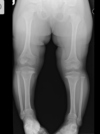

Masculino, 12 anos

Síndrome da sincondrose isquiopúbica assimétrica (Doença de Van Neck-Odelberg)

Variante da normalidade (em geral assintomático)

Crianças

Alargamento e radioluscência na sincondrose isquiopúbica, que simula neoplasias, infecção;